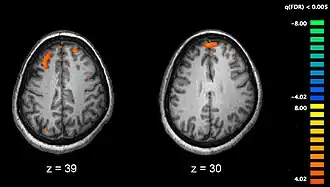

Phonological processing yields phonological codes (or representations) which are then used in speech processing to reach higher-level lexicon representations that are essential for auditory speech comprehension [6]. Strong empirical evidence shows the involvement of the posterior middle temporal lobe regions in accessing lexical and semantic information [6][8][11]. Lesion studies of the posterior temporal lobe have also supported this evidence. Elizabeth Bates and her colleagues studied 101 left-hemisphere aphasic patients and found that lesions to the middle temporal gyrus (MTG) most accurately predicted auditory comprehension deficits, with a significant deficit also observed with dorsolateral prefrontal cortical lesions. Whereas, lesions to the insula and arcuate/superior longitudinal fasciculus affected verbal fluency the most [12]. Functional magnetic resonance imaging studies (see Figure 3 for an example of an fMRI scan) have further implicated the posterior middle temporal lobe regions in semantic processing. In a semantic decision task in research conducted by Jeffrey Binder and colleagues, activations were found in both sides of the STS and almost all of the MTG in the left hemisphere. They also found that this activation spread ventrally across the inferior temporal gyrus (ITG). The authors found further activations in the angular gyrus, anterior and posterior cingulated gyrus, portions of the precuneus, retrosplenial cortex, and cinglulate isthmus in the left hemisphere; as well as subcortical activations in the anterior thalamus in the left hemisphere. [11]. Many positron emission tomography (PET) studies (see Figure 4 for an example of a PET scan) examined the activated areas in response to semantic processing. They too found left lateralized non-STG temporparietal regions; including the MTG, inferior temporal gyrus (ITG), and the angular gyrus [13] [14][15].